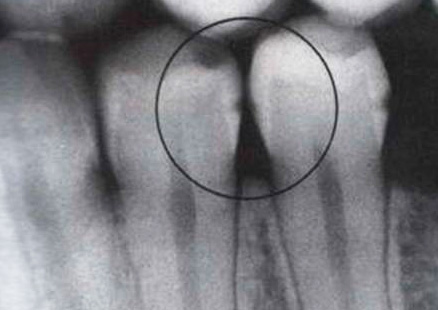

- Radiografia, in cui le cavità profonde colpite dalla carie hanno un colore molto più scuro.

Nella foto sotto - la carie interna sui tessuti sotto lo smalto distrutto. Questo è un tipo tipico di malattia che si sviluppa all'interno del dente. Le aree scure della dentina interessata sono chiaramente visibili:

È il cambiamento di colore dei tessuti danneggiati dalla carie che è il principale segno diagnostico della malattia. Nella stragrande maggioranza dei casi, è proprio sui punti neri sullo smalto o sulle fessure che il medico fa in modo inequivocabile la diagnosi di carie.